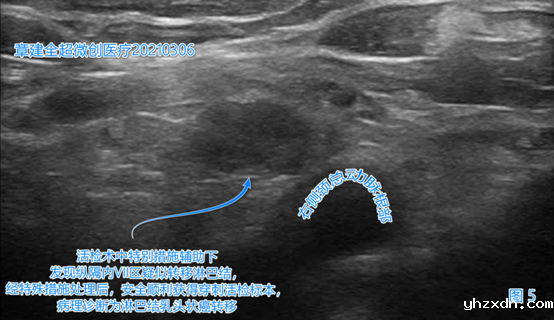

左侧颈部VI(6)区(图4)、

右侧颈部VI(6)、右侧颈部VII(7)区(图5)出现了疑似癌转移的淋巴结。